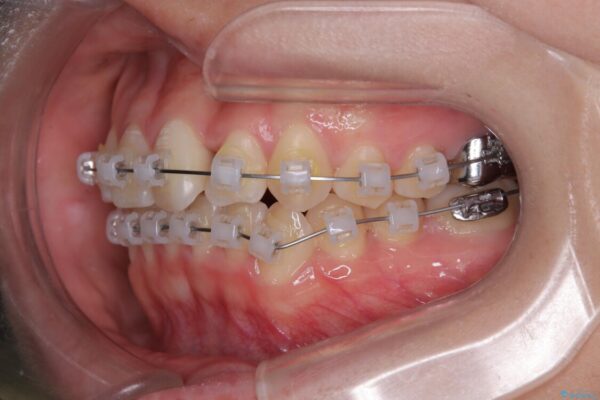

治療方法としては、装置の目立ちにくさと費用面のバランスを考慮して、プラスチック製のクリアブラケットとメタルワイヤーを組み合わせた矯正装置を使用することにしました。

治療途中

• 前歯のねじれ・ガタガタを10か月で改善!20代女性の矯正治療|クリアブラケットでむし歯になりにくい歯並びへ改善 治療途中画像